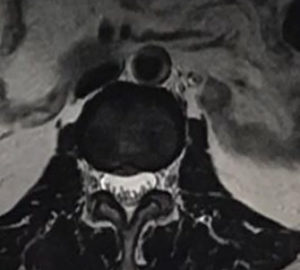

醫生會透過了解病史、檢查肌肉及神經反射狀況來尋找致病原因,也會讓病人做些引起疼痛的動作供醫生作判斷,若有需要也會要求患者做磁力共振掃描(MRI),以檢查椎間盤突出有否牽涉周邊脊椎神經線受壓。亦可從磁力共振掃描看見椎間盤失去水份及膠原蛋白而變黑,這就是退化性椎間盤的變化。

從磁力共振掃描看見椎間盤會因為失去水份及膠原蛋白而變黑,這就是退化性椎間盤的變化。